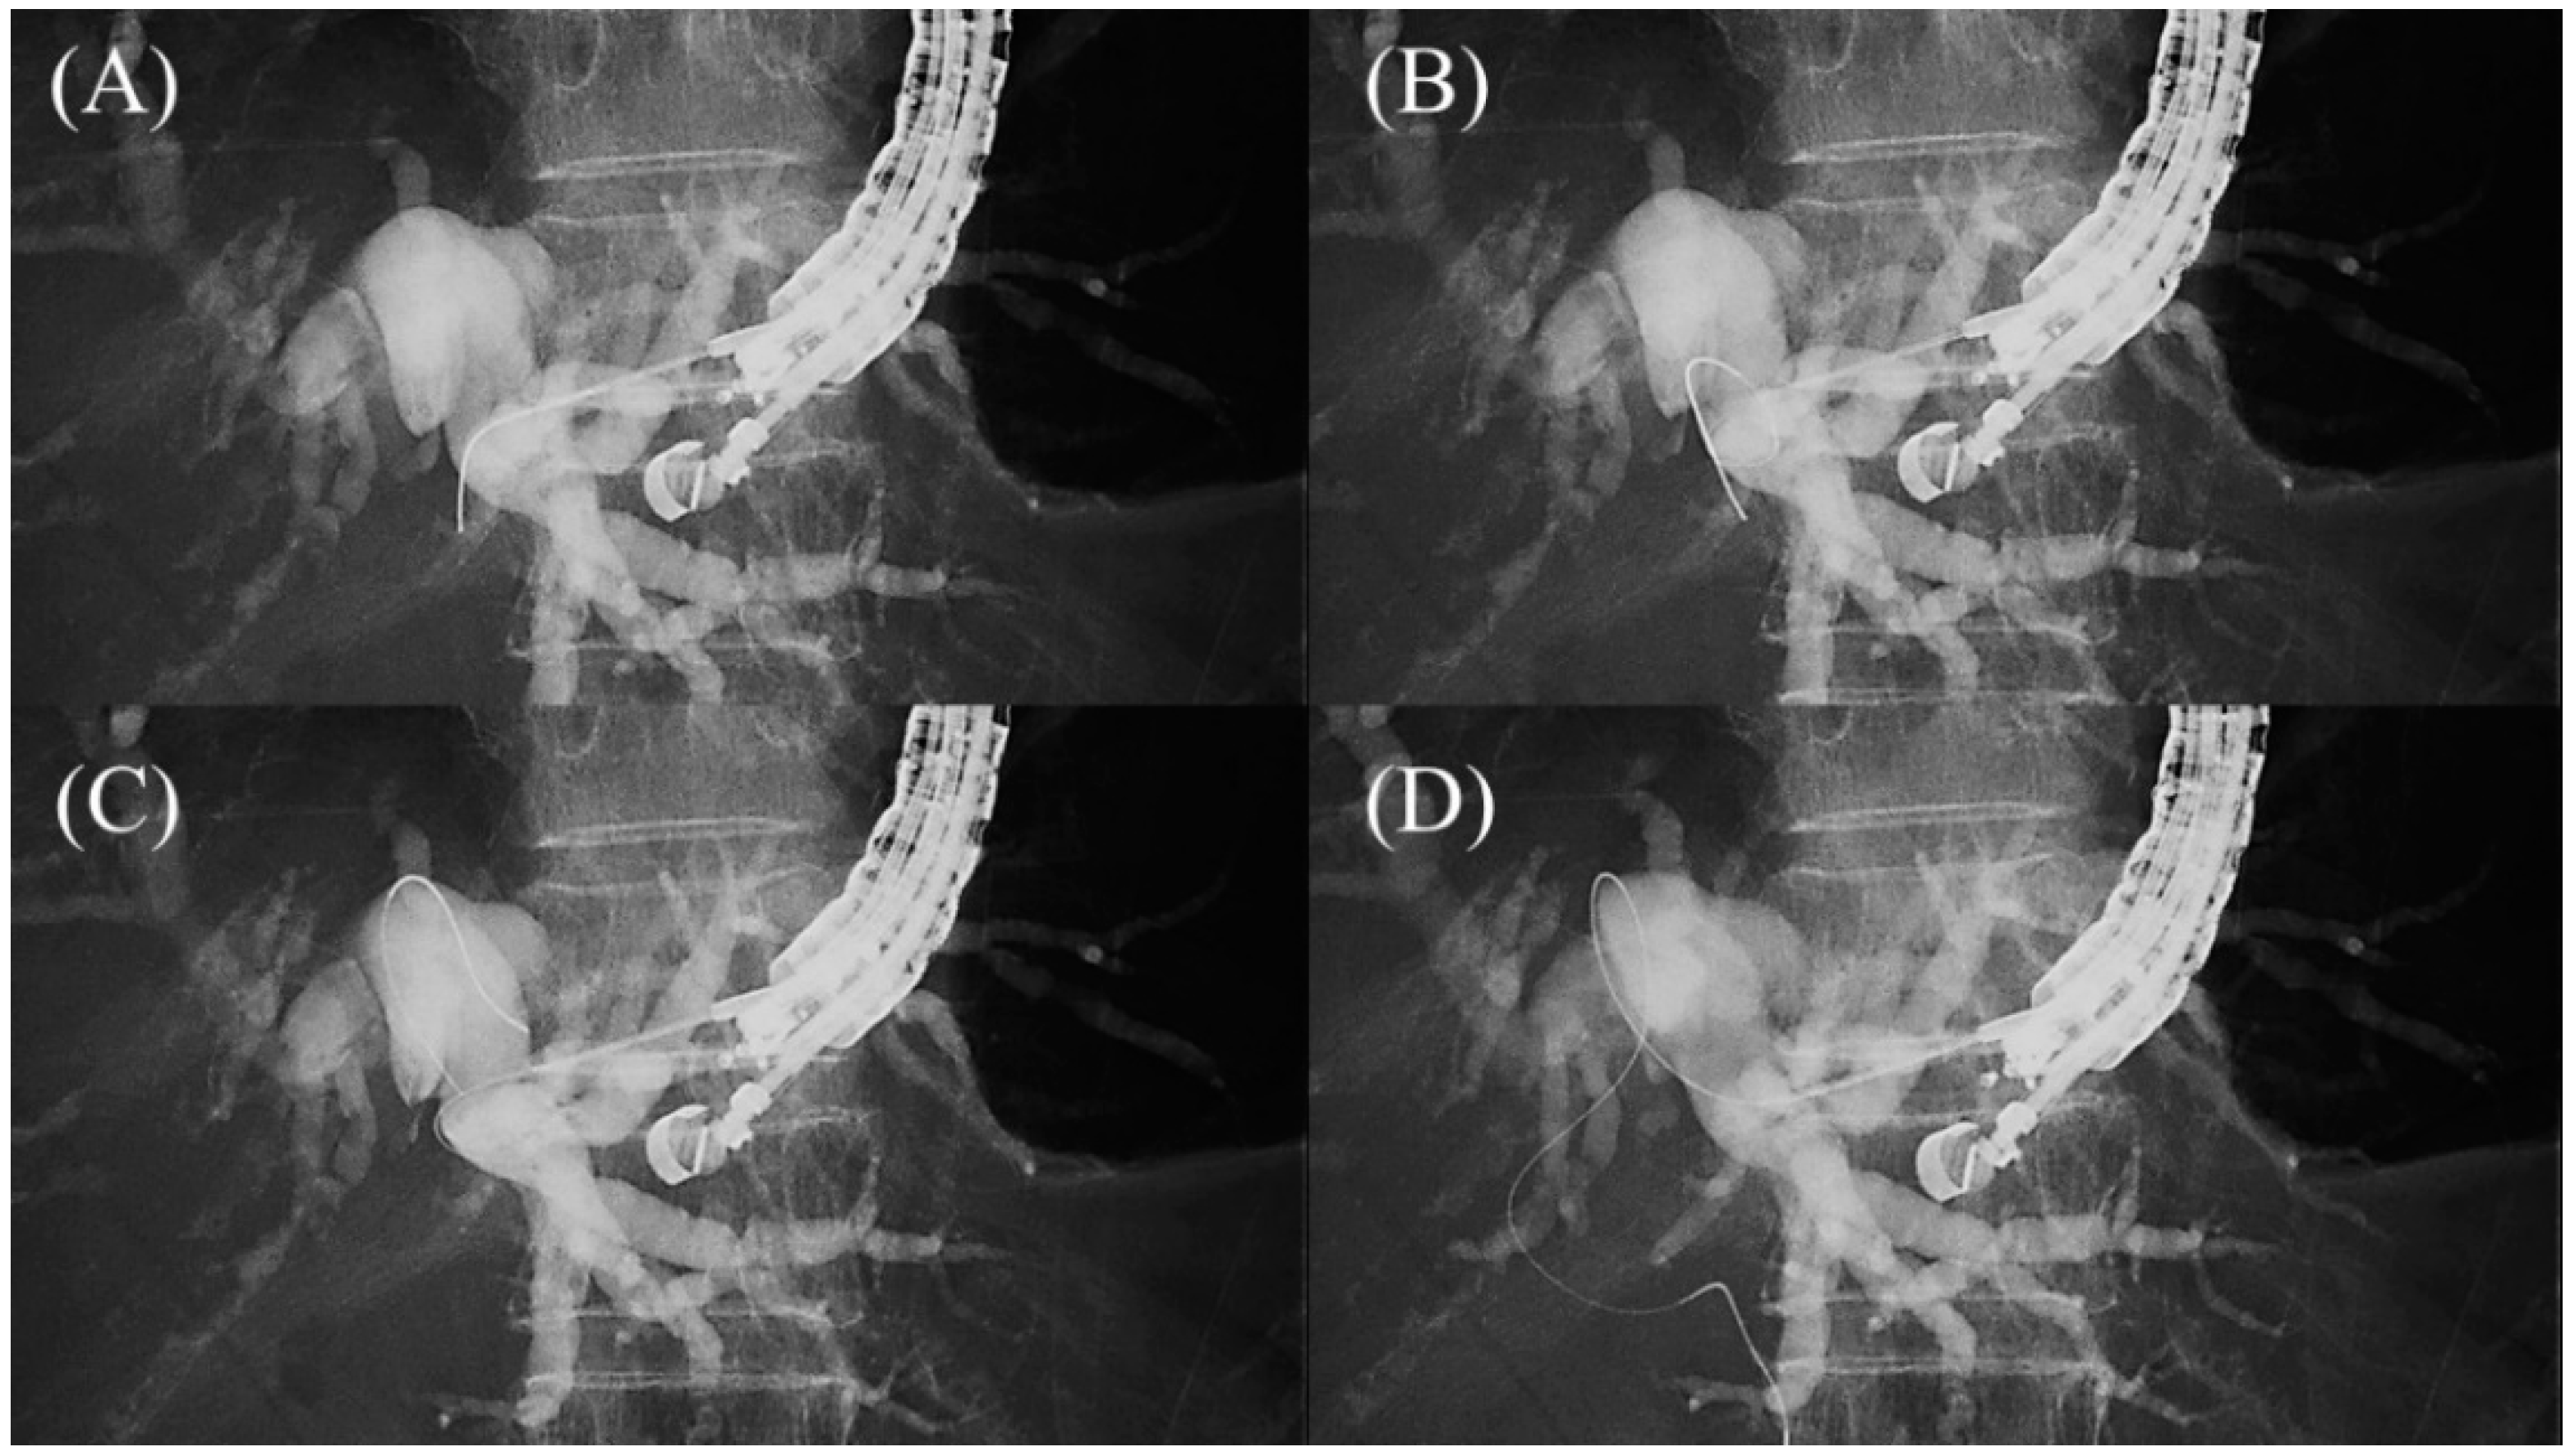

The guidewire is advanced through the needle, and once it enters the bile duct, it is slowly and carefully advanced with gentle rotation to guide it toward the hilar region. If the guidewire is unintentionally advanced to the peripheral side, the “Loop technique” should be attempted first. Push the guidewire with rotation, and when the tip of the guidewire is caught on a lateral branch (

Figure 7A), push the guidewire further. Since the tip of the guidewire is fixed, the body of the guidewire will bend with the pushing force and form a loop (

Figure 7B). If the loop is facing the hilar region, the guidewire can be advanced to the hilum by pushing further (

Figure 7C,D). If the “Loop technique” fails, the “Moving scope technique” is an alternative to change the direction of the guidewire, where pushing the scope while turning the large wheel upward may change the direction of the needle to the cranial side, allowing the guidewire to proceed toward the hilum

[29] (

Figure 8A–C).

Figure 7. Loop technique for redirection of a guidewire. If a guidewire is unintentionally advanced to the peripheral side, push the guidewire with rotation. When the tip of the guidewire is caught on a lateral branch (A), the guidewire will bend and form a loop by pushing force (B). If the loop is facing the hilar region, the guidewire can be advanced to the hilum by pushing further (C,D).